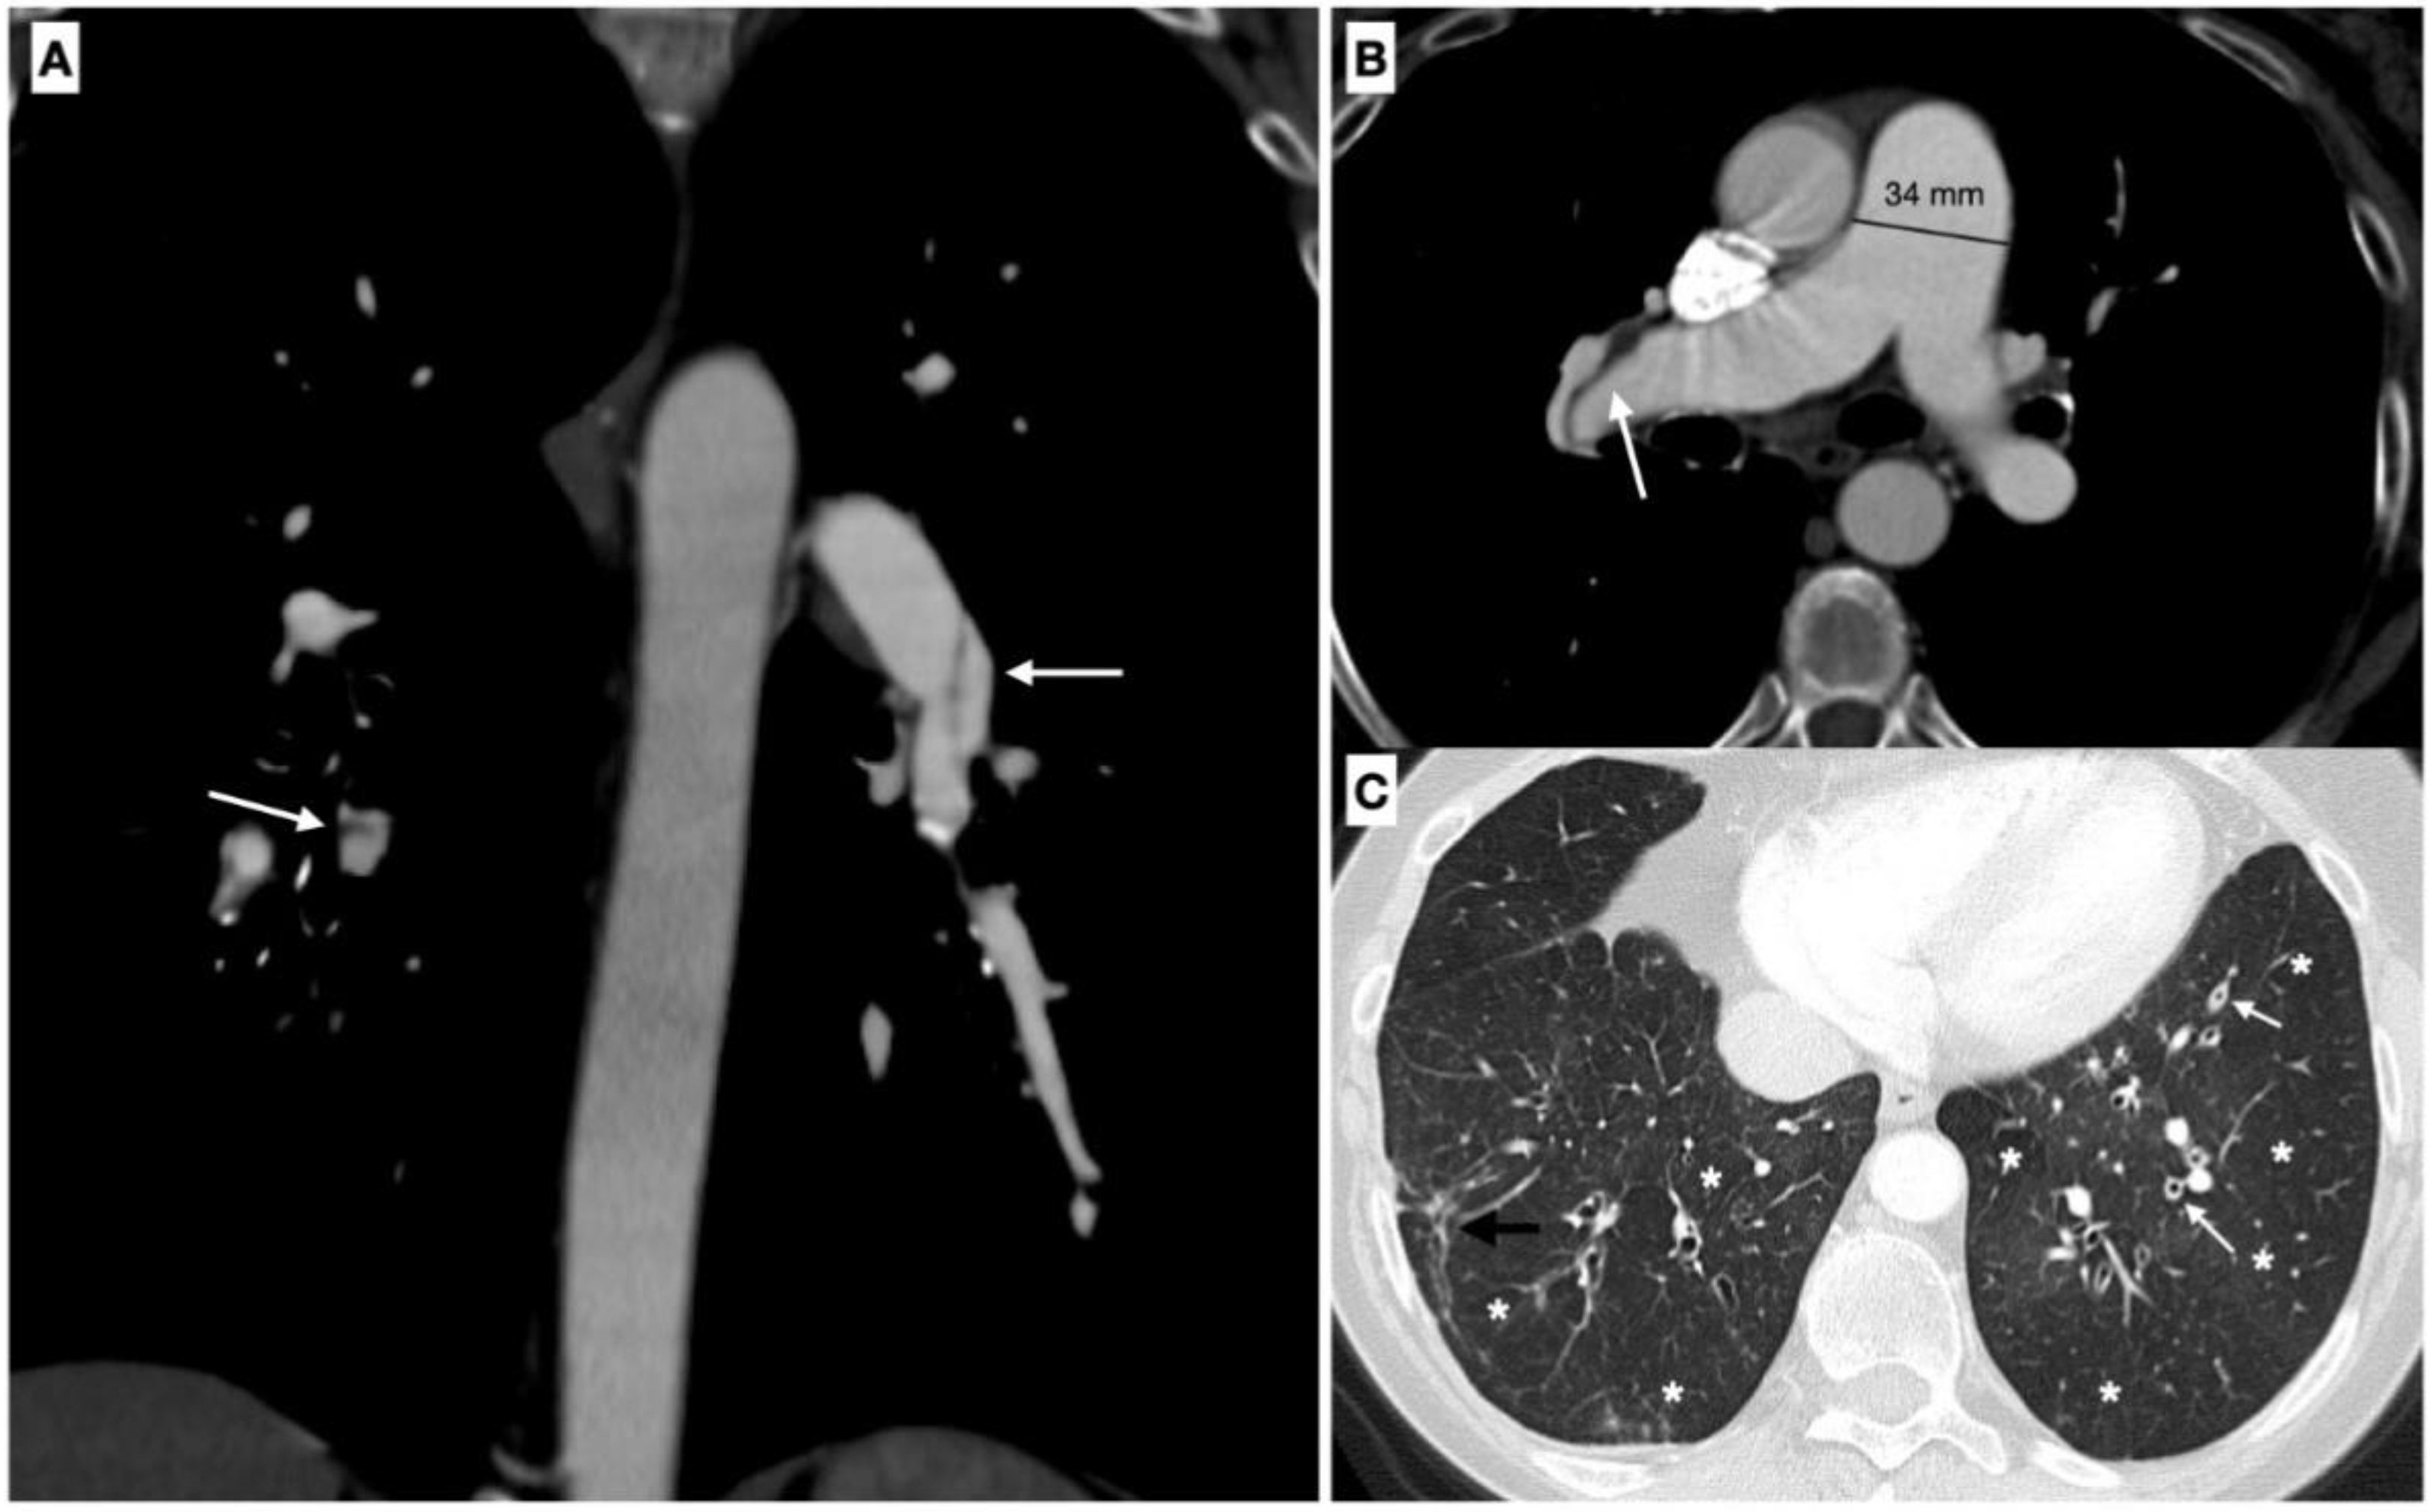

2.7. Pulmonary Function Tests